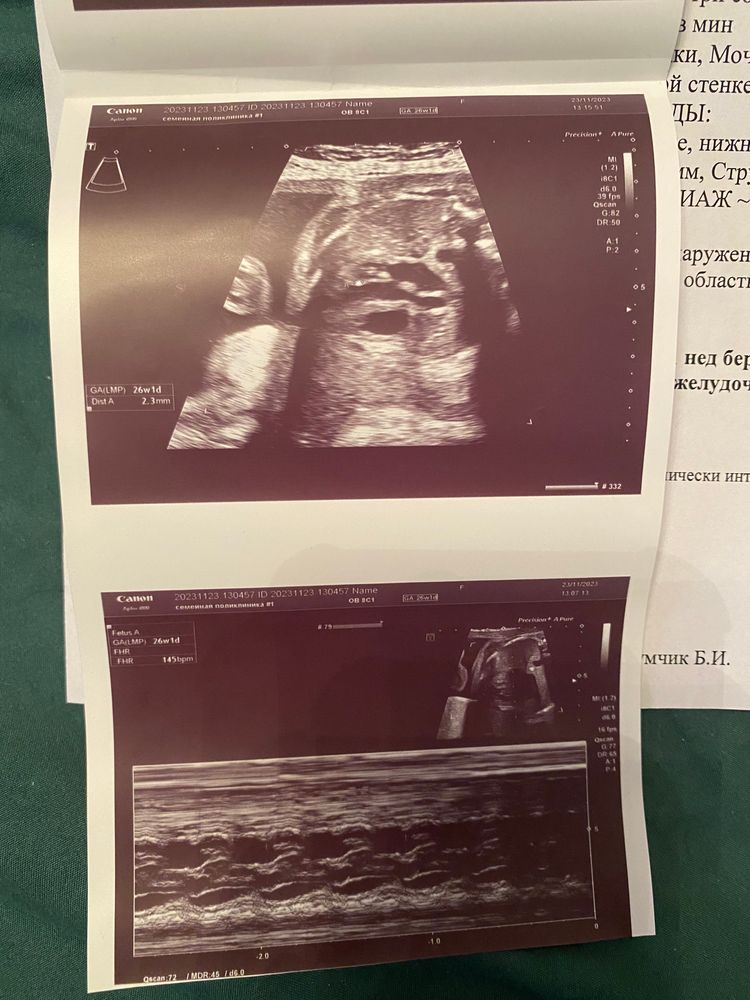

Экспертное узи в 26 недель или ГЭФ или хорда 2.0.

Размеры ШМ. УЗИ 33 недели, НМПК 1а